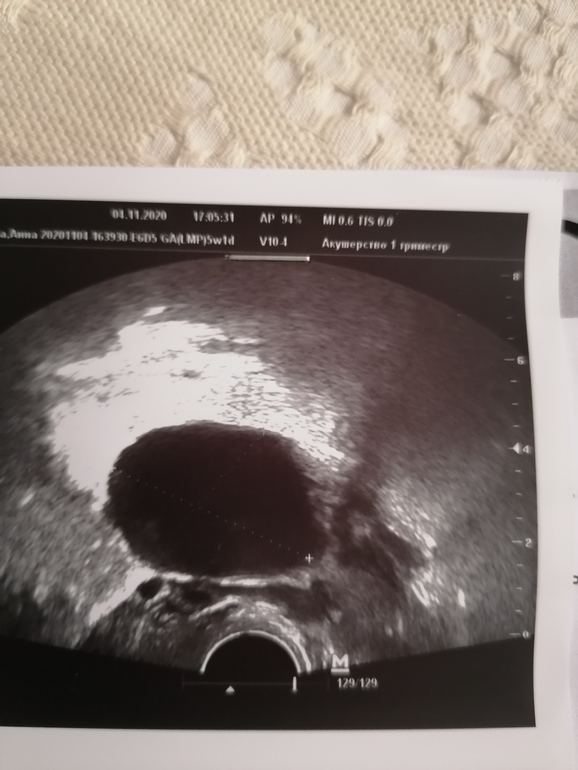

В ПЯ большая фоликулярная киста 4.67см. На узи сразу после овуля в ПЯ был фолик 12мм и он собака не сдался, а перерос в кисту, от сюда и боли. Врач сказала, что никакого секаса и быть осторожнее не поднимать ничего и не прыгать, не бегать. К 12 неделям должна рассосаться. Как-то так.

Вот киста